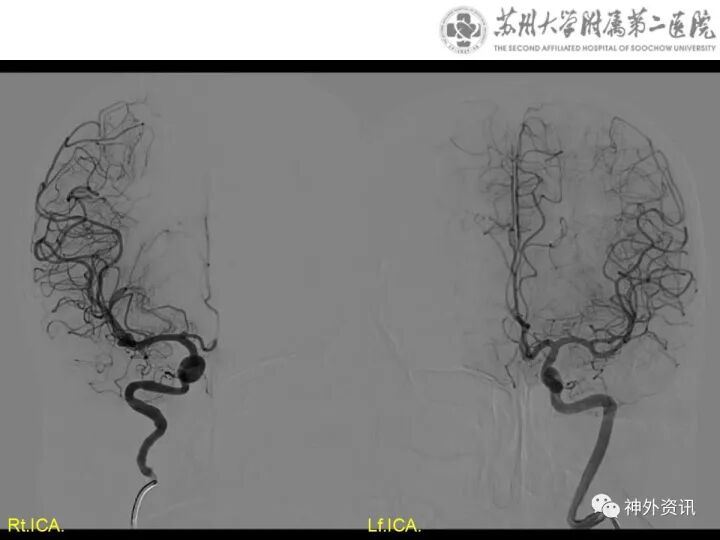

颅内多发动脉瘤右翼点锁孔入路夹闭术